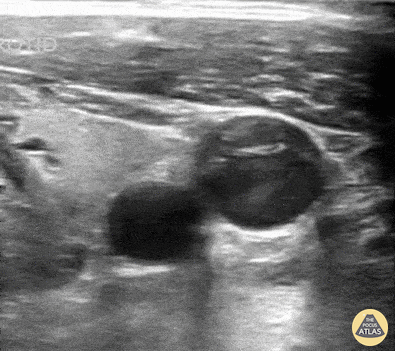

Vascular - Swirling Blood in the Internal Jugular Vein after Aortic Dissection

Patient presented with near syncope and unilateral neck pain. Ipsilateral neck ultrasound revealed swirling blood within the IJ; subsequent evaluations identified etiology to be a thoracic aortic dissection contributing to pericardial effusion and cardiac tamponade! Peter Weimersheimer, MD. Director EM POCUS at ULA @VTEMSONO